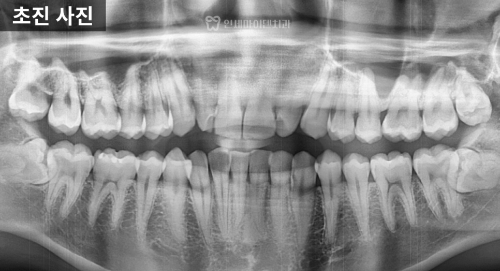

20대 교정 진단, 삐뚤빼뚤한 앞니

이번 케이스는 20대 중반으로,

앞니가 돌아가 있고 아래 앞니가 안쪽으로

많이 쓰러져 있었습니다.

진단해 보니

단순히 치아 배열의 문제가 아닌

위턱이 전체적으로 좁고

치아들이 안쪽으로 쏠려 있었으며,

특히 두 번째 앞니는 크기가 작은

왜소치 형태를 띠고 있었습니다.

사랑니는 매복되어 있었고

발치가 필요한 상태였지만

전반적인 치근 상태는 양호했습니다.